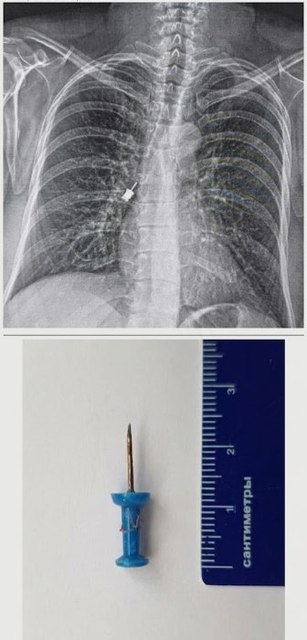

Канцелярська кнопка у підлітка: Через необережність кнопка потрапила до дихальних шляхів. Раптовий кашель став сигналом для негайної госпіталізації. У нашому центрі предмет було оперативно видалено, підліток пройшов повний курс лікування та вже повернувся додому.

Стоматологічна викрутка: Навіть під час медичних маніпуляцій може статися непередбачуване. Інструмент для імплантації випадково потрапив у дихальні шляхи пацієнта. Лікарі нашого центру успішно впоралися з цим складним завданням.